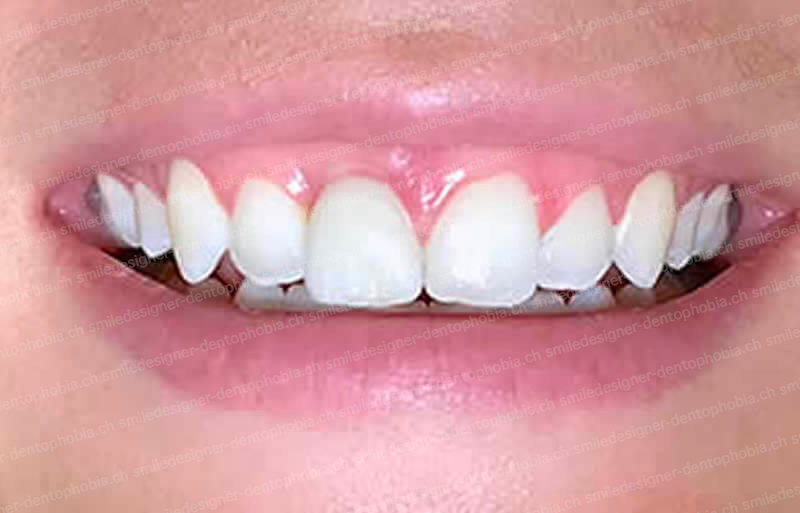

Cas clinique « SMILE RED FLAG MEI » : Traitement de remplacement d’une dent du sourire par un implant en Mise en Esthétique Immédiate. Visualisation de la version définitve de la couronne sur implant avec un cosmétique en céramique.

Après la guérison des tissus mous (gencive) et durs (os alvéolaire), la couronne céramique esthétique a été installée sur l’implant.

Le maintien de l’esthétique du sourire dépend en grande partie de la reconstruction des tissus gingivaux entourant la couronne céramique esthétique et de l’os autour de l’implant.